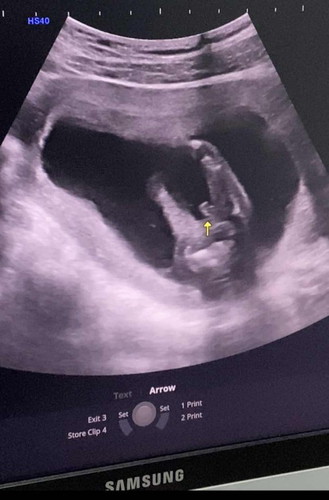

เบบี๋ในวัย 17 week นู๋เป็นเด็กผู้ชายนะครับ พ่อพ่อดีใจมา 😅🤰🏻👼🏻 ทีแรกลุงหมอบอกลูกสาวมาตรวจรอบนี้กระจู๋โผล่แล้วครับ 😂😂